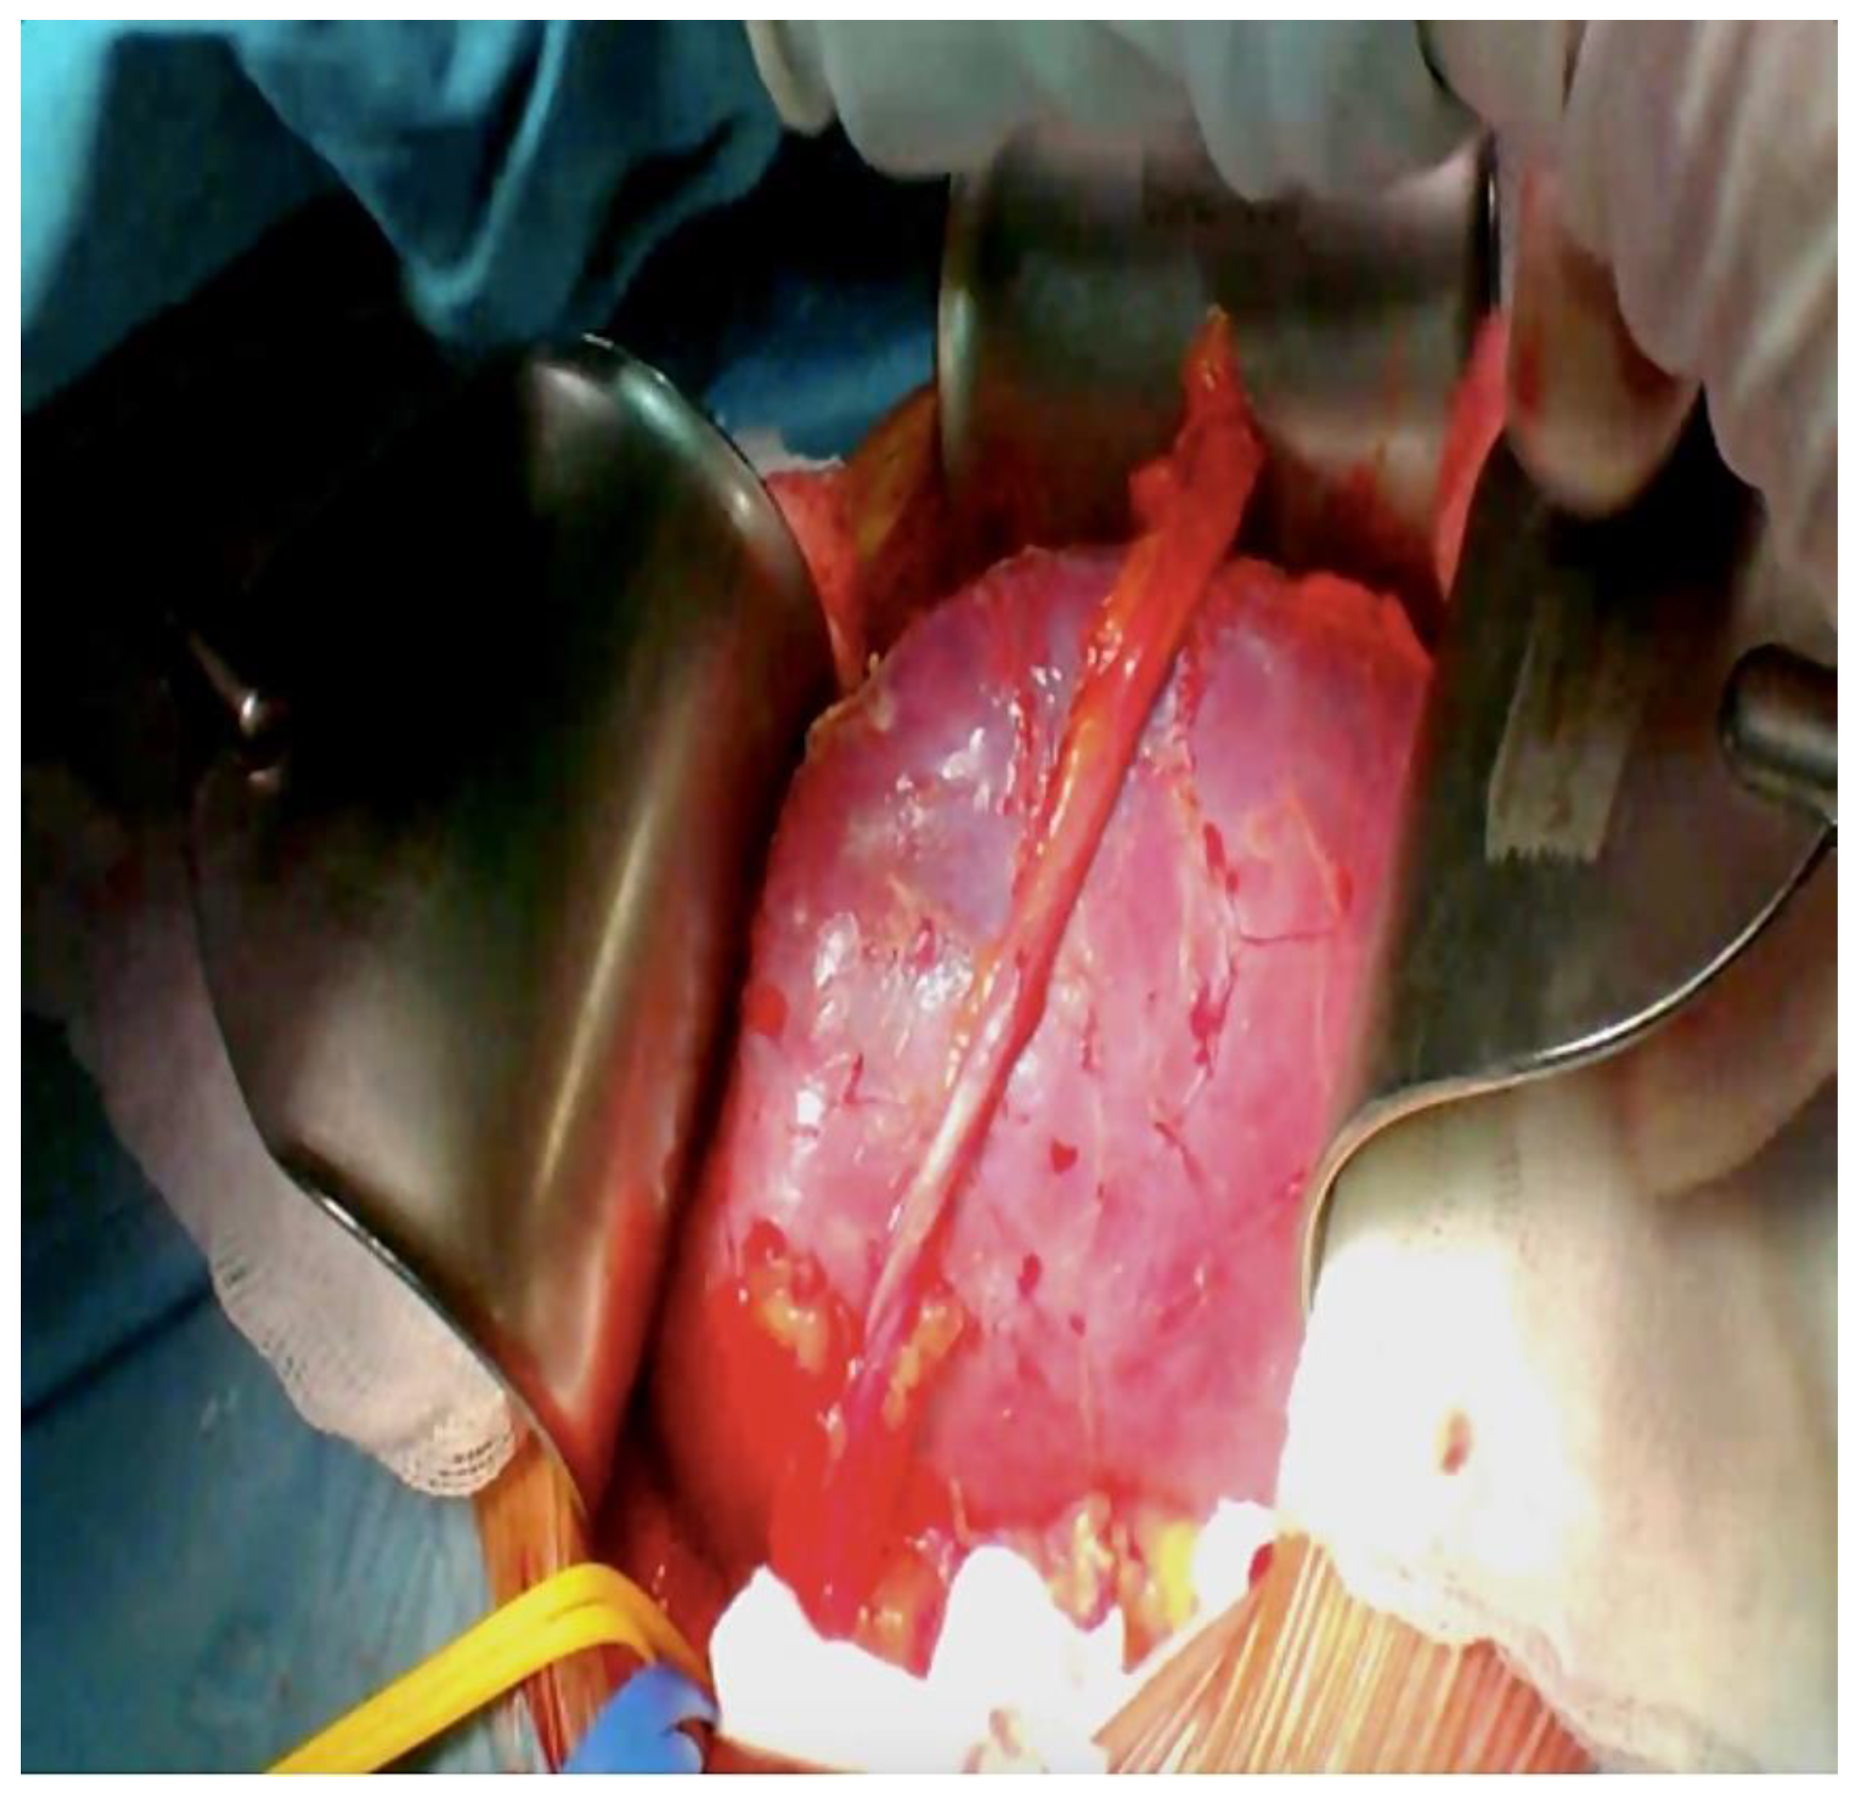

3. Methods and Procedure